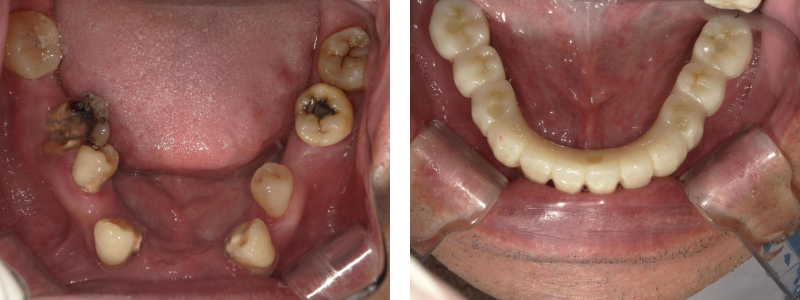

治療内容 60代男性 重度虫歯を抜歯しインプラント埋入

期間 3日間(インプラント埋入)

費用 990,000円

(インプラント2本+被せ物4本)

注意点/副作用 外科処置が必要・全身状態によりできない場合がある。